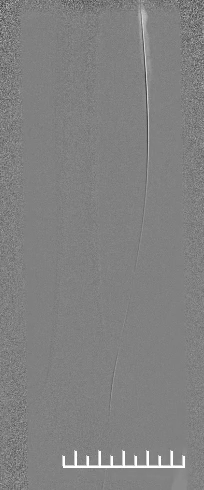

1.造影评估:左股动脉翻山入路,经鞘管造影见右股浅动脉中下段局限重度狭窄,远端股腘动脉、膝下动脉延迟显影,血流流速缓慢(图2,3,4)。

(图2)

(图3)

(图4)